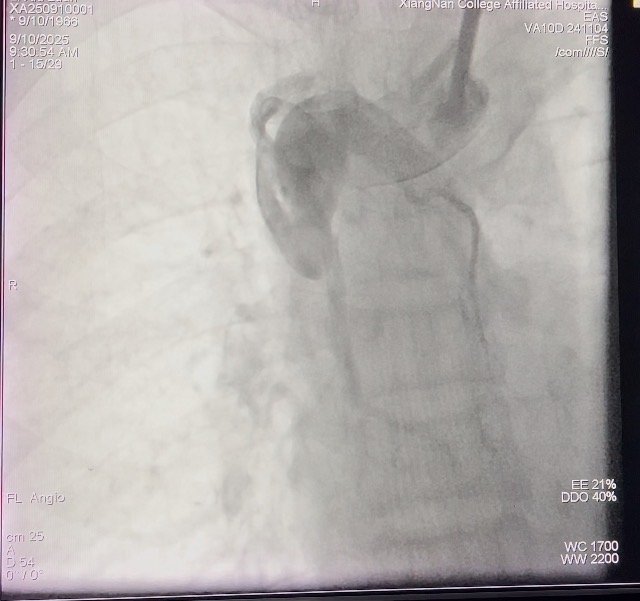

闭塞开通前的影像